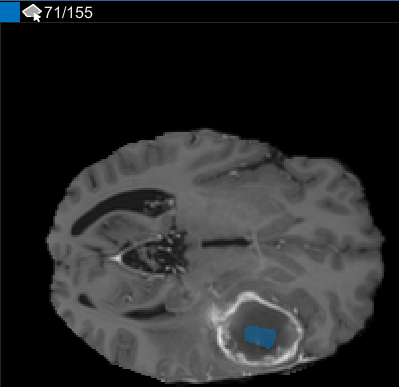

После использования интерполяции проверяйте отдельные срезы, чтобы видеть, создала ли интерполяция удовлетворительные ROI. Обратите внимание на то, что ROI на срезе 71 не заполняет целый объект, который вы хотите сегментировать. Можно вручную настроить ROI с помощью инструмента Paint Brush. В качестве альтернативы можно использовать один из инструментов во вкладке Automate. Например, можно использовать Активные Контуры, чтобы вырастить ROI на срезах, где это не заполняет полный размер опухоли.

В панели Среза перейдите к срезу, где объект сначала появляется, и начните помечать объект на каждом срезе с помощью инструмента для рисования. В следующем рисунке этот пример использует инструмент Paint Brush, чтобы пометить опухоль. Как ранее, можно чертить объект на каждом срезе, где это появляется, или используйте инструменты интерполяции, чтобы привлечь несколько срезов автоматически. После интерполяции можно использовать инструменты для рисования, такие как Средство стирания, чтобы изменить автоматизированную сегментацию на каждом срезе.